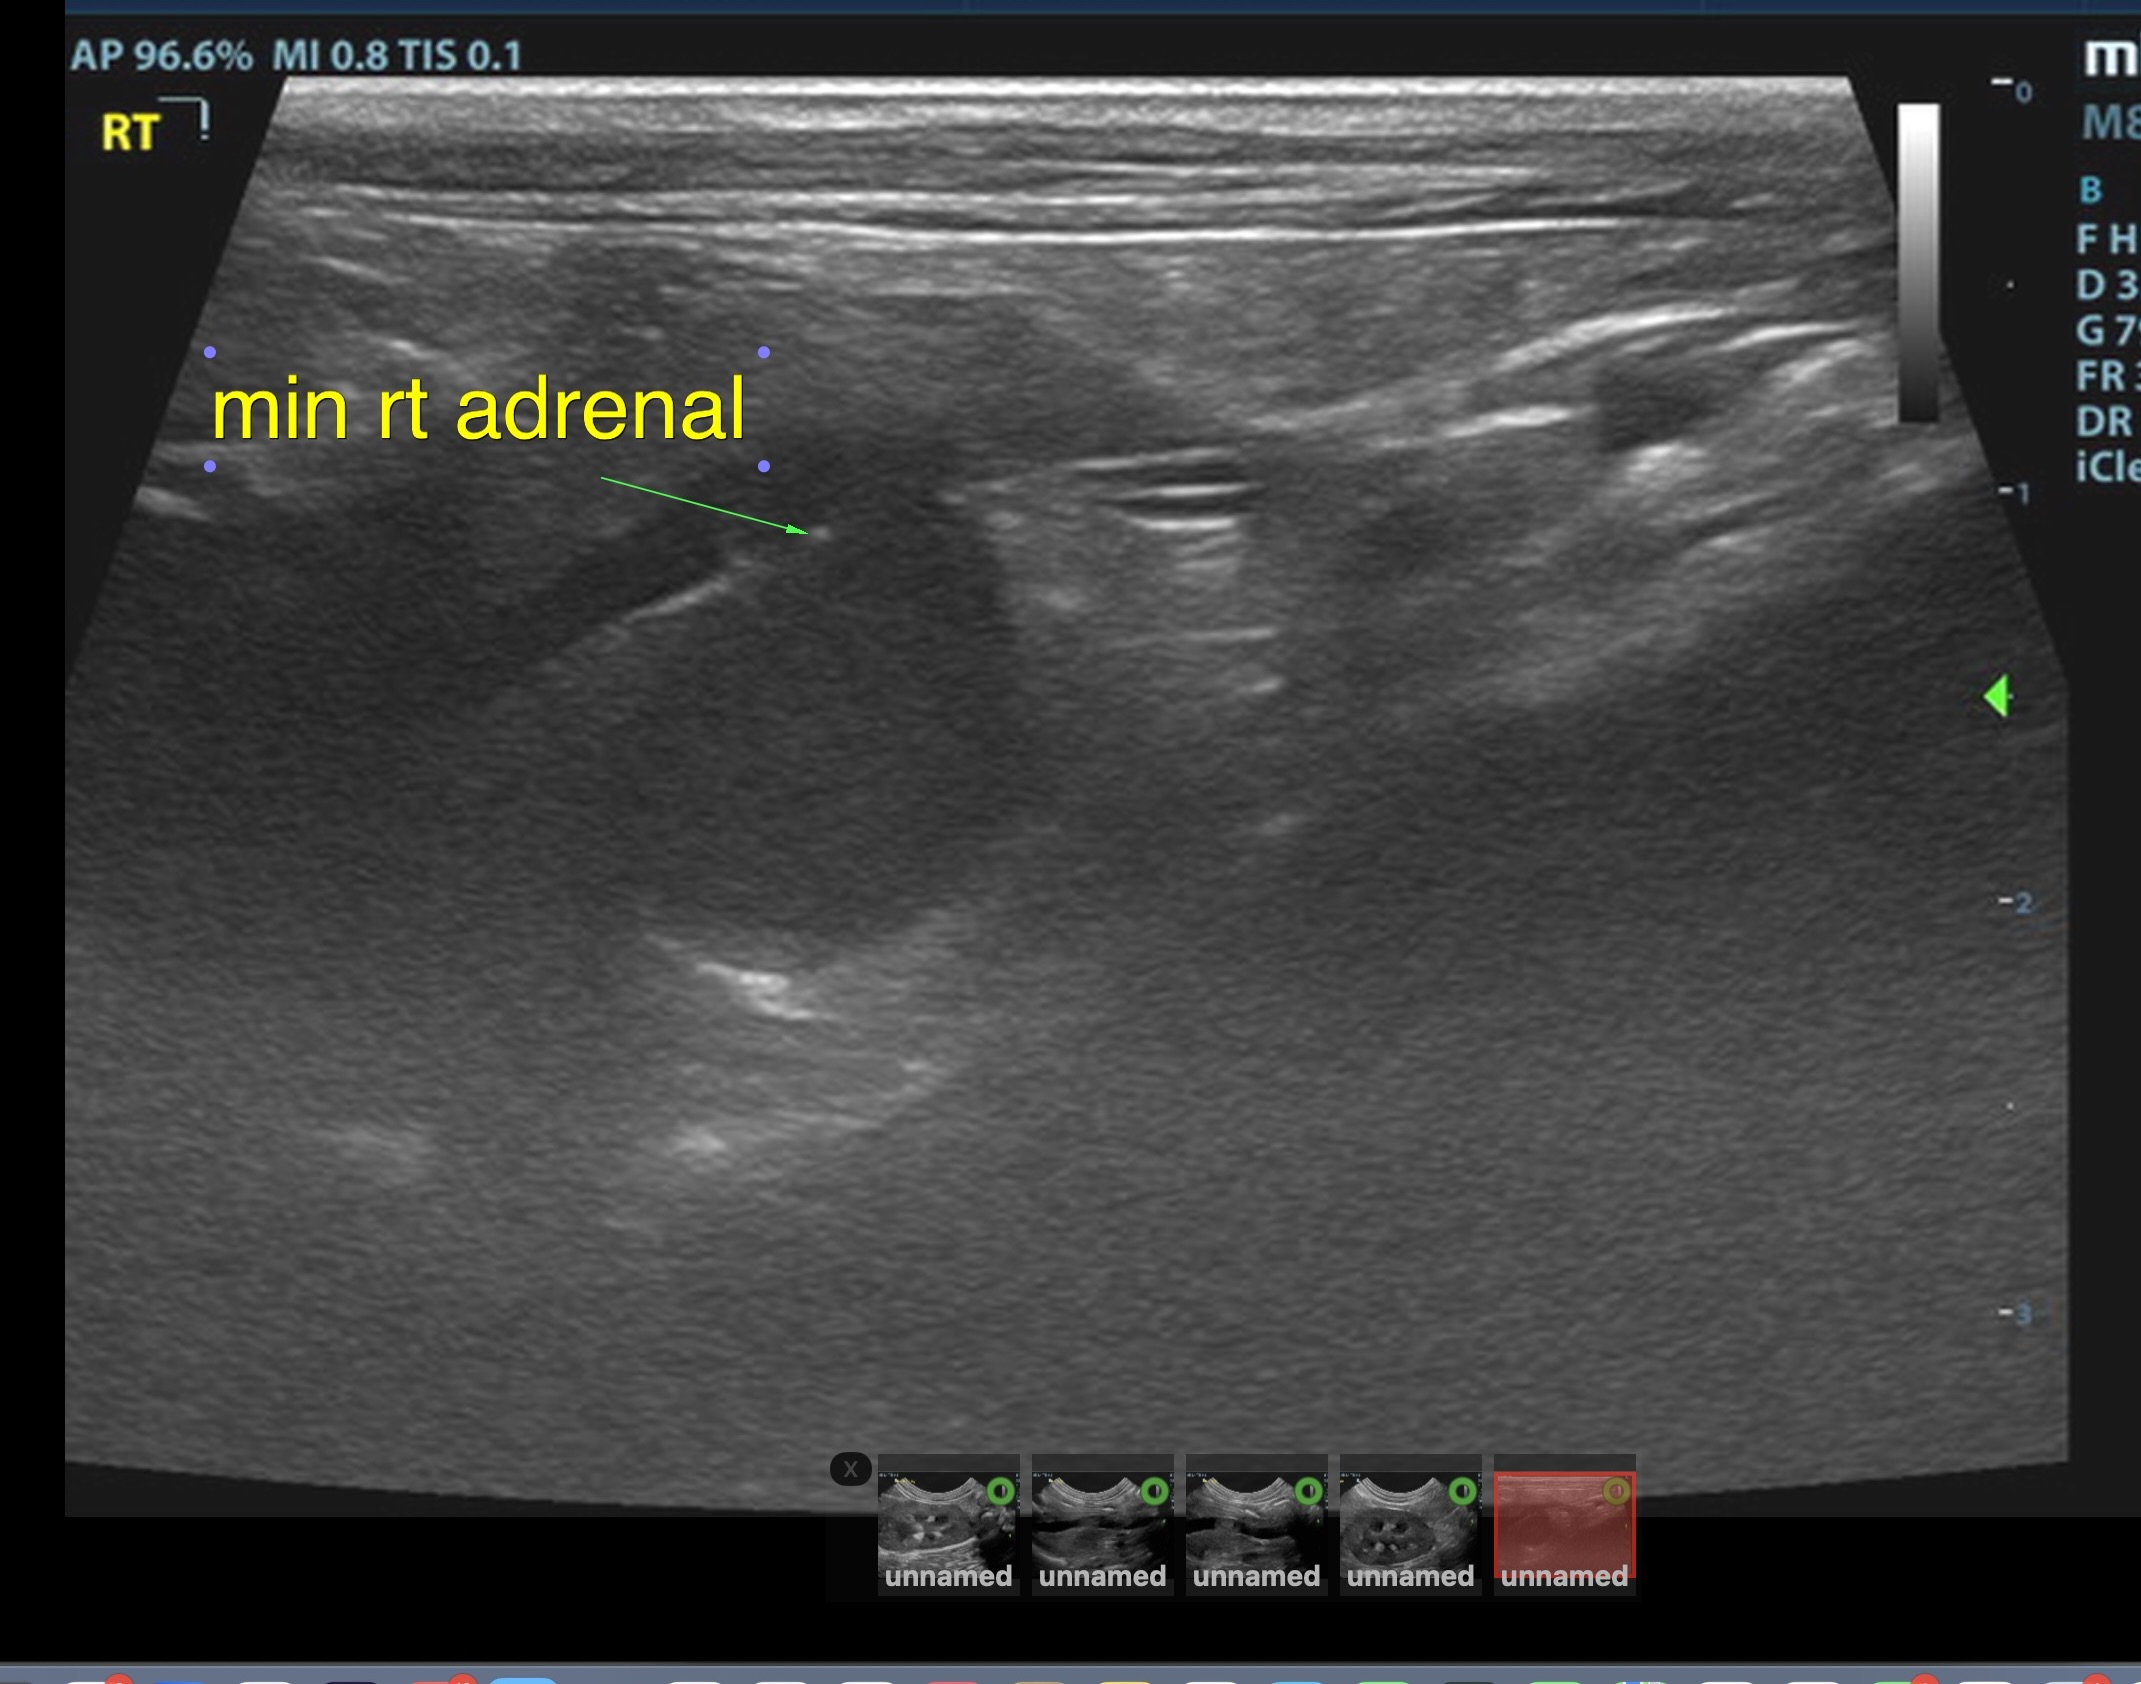

The right adrenal was enlarged and irregular, measuring 0.77 cm at the cranial pole and 0.30 cm at the caudal pole, with a caval invasion of 0.85 cm. Minor areas of mineralization noted. The left adrenal gland was recognized as normal. Mild variable GI thickening and echogenic submucosal changes. Some loss of renal curvilinear patterns regarding the capsule and cortico-medullary junction; increased echogenicity, mineralization.  Some hepatic parenchymal remodeling.

• Invasive right adrenal mass